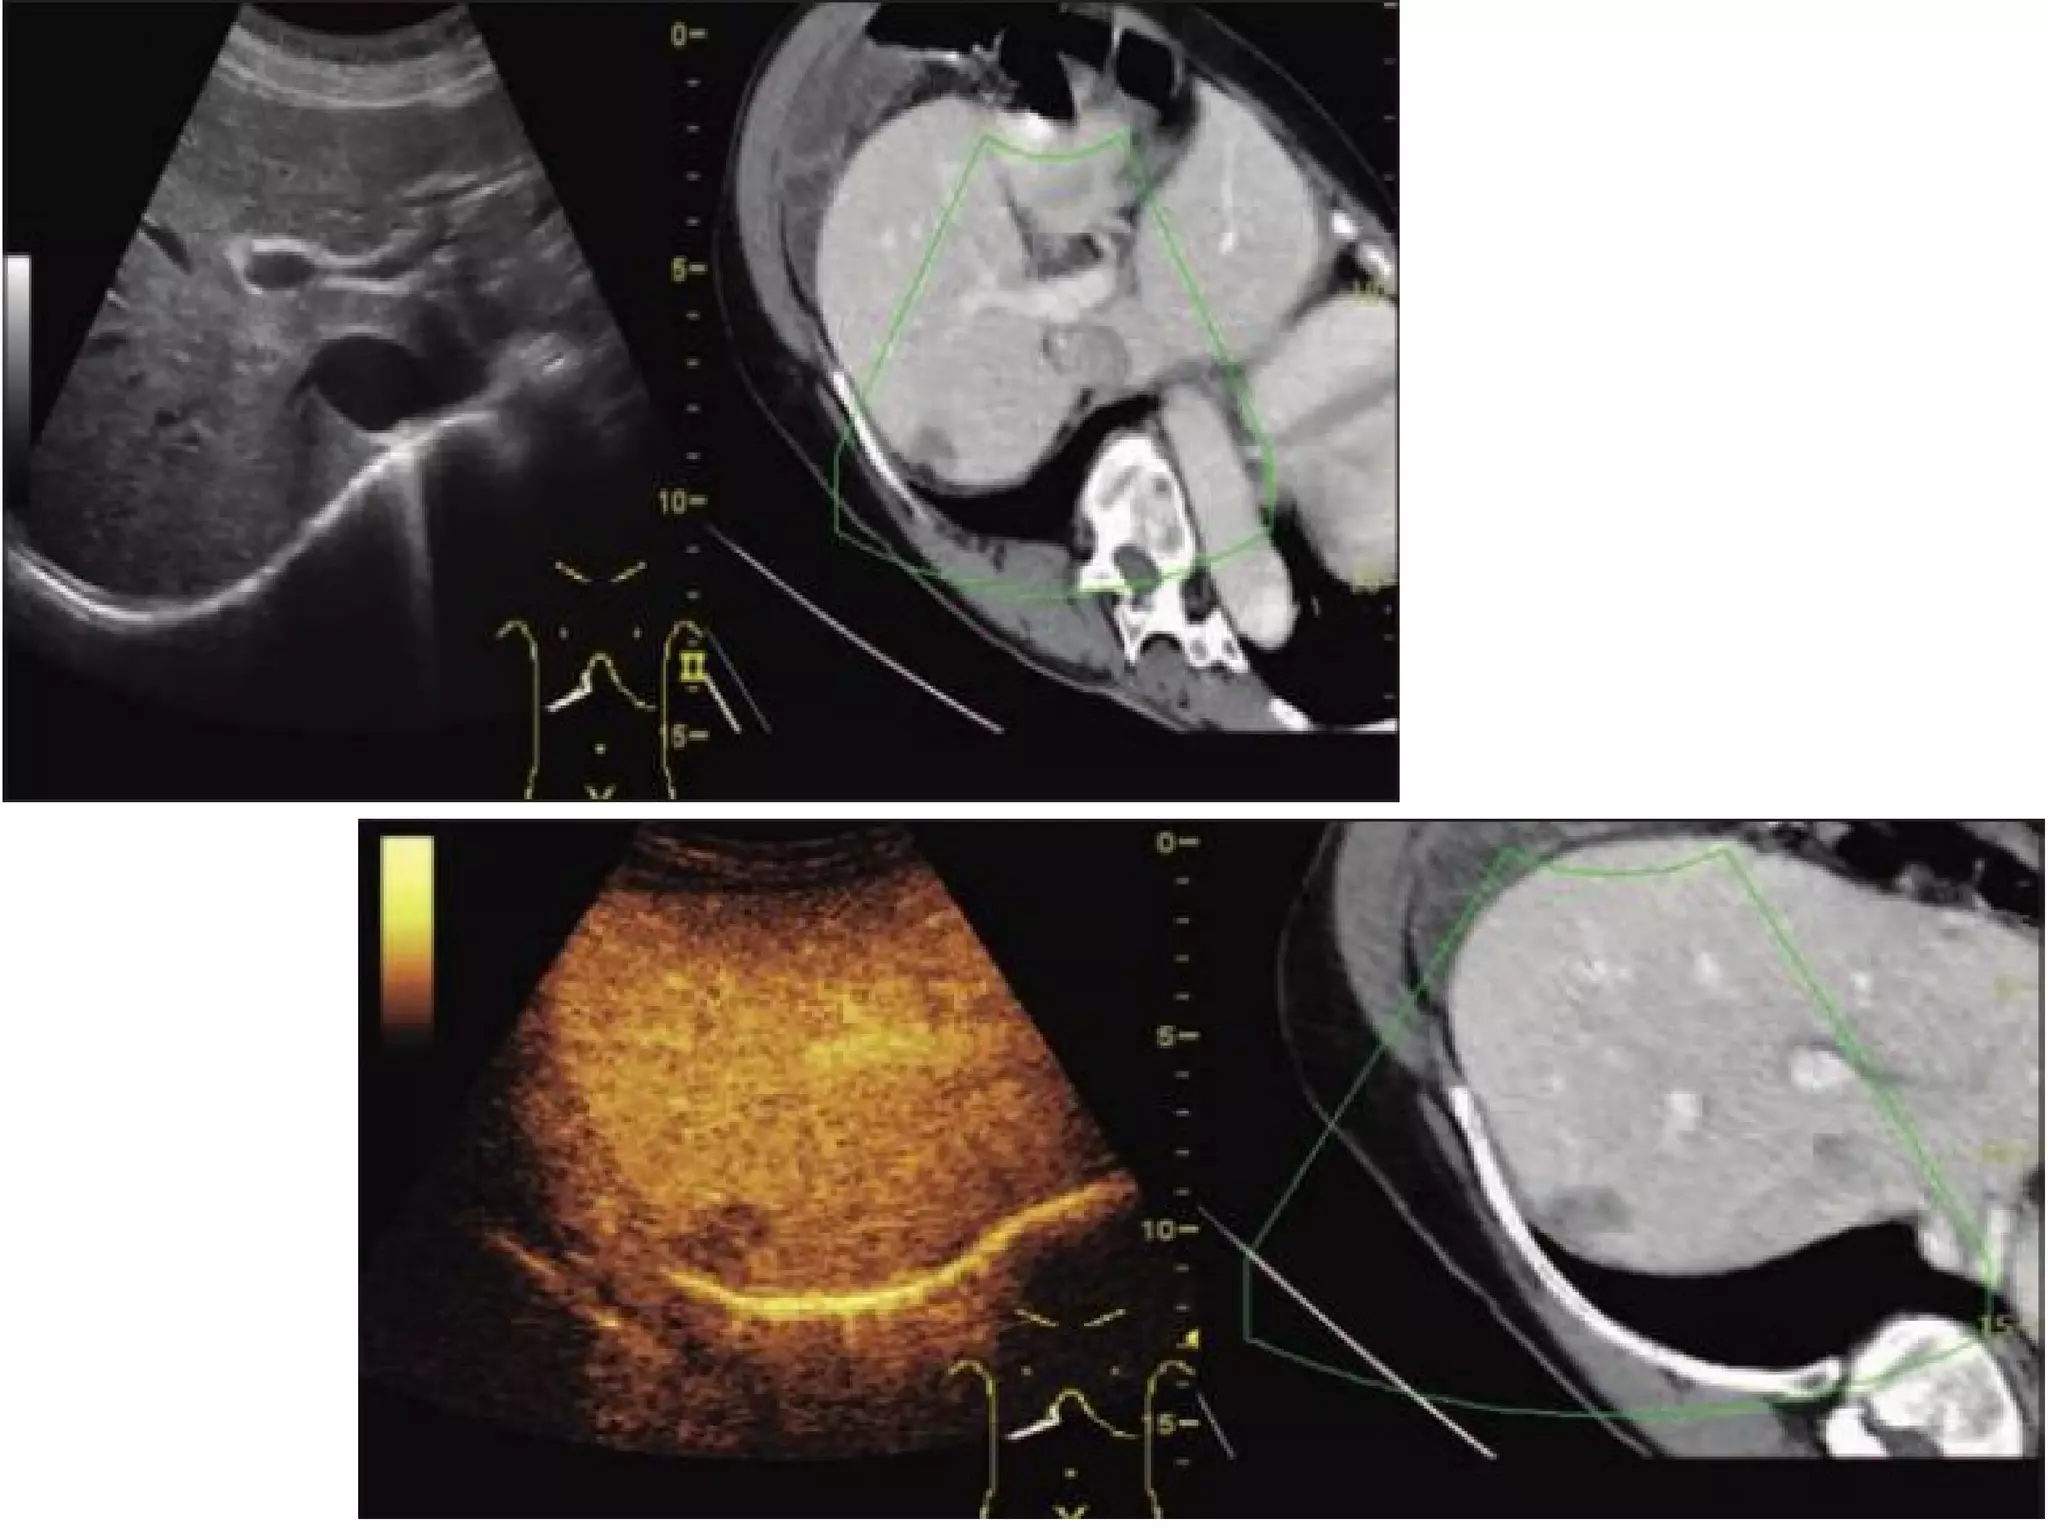

FUSION IMAGING

• Fusion imaging or hybrid imaging means

combination of two imaging techniques.

• This can be in the form of ultrasound with MRI

or CT

• or it can be fusion of (ultrasound, CT or MRI)

with molecular imaging technique like SPECT or

PET

The advantages of incorporating ultrasound in image

fusion consist in the :

• real-time images (which enable image-guided

intervention),

• the lack of radiation to both patient and staff,

and

• the possibility of comparing findings on one

modality with another modality .

Software for fusion of real-time ultrasound images

with CT, MRI, or PET/CT is incorporated in several

high-end ultrasound systems.

STEPS OF FUSION

• During examination ultrasound screen is seen as split images

with virtual reconstructed CT/MR image on one side and

currently acquired USG image on other side of the screen.

• An attempt is made to match these two images with each

other using some clearly visible anatomic landmark (e.g.

portal vein bifurcation, superior most margin of kidney or

the lesion itself, etc.)

• For fusion imaging variety of tracking methods are used,

common are the optical tracking system and

electromagnetic tracking system.

Clinical applications

• Isoechoic lesions not well appreciated on grey

scale.

• Previously ablated lesions with recurrence not

well visualized.

• Interventional treatment is easy.